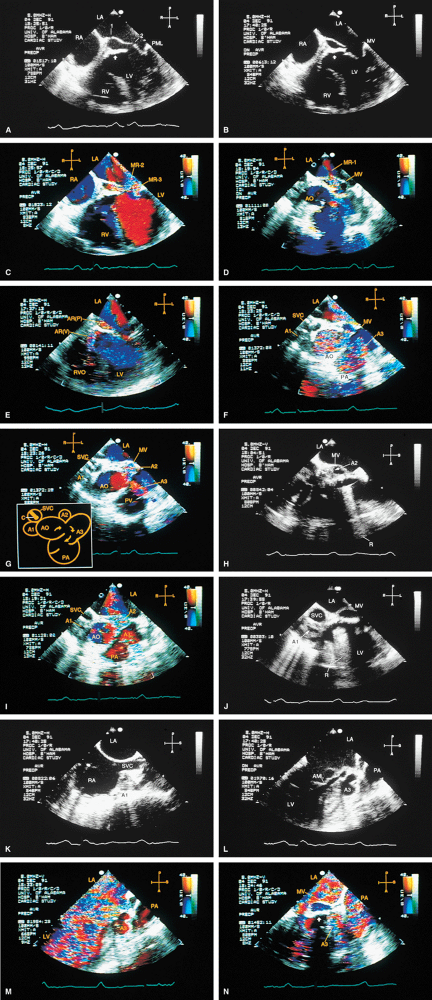

FIGURE 5.46. Homograft aortic prosthesis: degeneration/stenosis/prolapse/regurgitation/infection. A. Thickening and calcification of the prothesis (P) with marked restriction of opening during systole is indicative of stenosis. B. Color Doppler shows a very narrow jet (arrowheads) originating from the prosthesis in systole, also indicative of obstruction. C–F. Another patient with prosthetic (P) cusp prolapse (arrow in C), with severe eccentric aortic regurgitation (AR) and prominent flow acceleration (FA in D,E) on the aortic side. The AR jet is directed posteriorly and abuts against the anterior mitral leaflet. This valve was replaced with a St. Jude prosthesis (P)(F). Labels 1 and 2 indicate normal small prosthetic AR jets. Jet 1 originates anteriorly but is directed posteriorly (red). Conversely, jet 2 originates posteriorly but is directed anteriorly (blue). H, a small hematoma. G,H. Another patient with prosthetic (P) cusp prolapse (arrow) resulting in diastolic noncoaptation with the right coronary leaflet and producing severe AR (H). I. A patient with homograft prosthetic degeneration and severe AR (arrowheads). J. Color Doppler study of another patient with a homograft aortic prosthesis (P) showing severe AR (arrows). Note that the jet shows largely laminar flow with only a small amount of turbulence (variance) because of the nonperpendicular orientation of the ultrasonic beam relative to the direction of blood flow. K–N. A patient with homograft endocarditis. K. Marked diastolic prolapse (arrows) of the thickened prosthetic leaflets (P) with noncoaptation. A large vegetation (V) is seen prolapsing into the left ventricular outflow tract (LVOT) in diastole in L and into the aortic root in systole in M. N. Color Doppler examination shows severe AR and minimal pulmonary regurgitation (PR). O–V. Another patient with endocarditis involving a homograft prosthesis (P). The arrows in O, P, and Rshow prosthetic dehiscence and a large pseudoaneurysm posteriorly. Q–V. A fistula (F, arrows) from the aortic root into the RV and an abscess cavity (AB in S and T) are seen. V.Color Doppler–guided continuous wave Doppler shows flow through the fistula throughout the cardiac cycle. AB, abscess; AO, aorta; LA, left atrium; LVO, left ventricular outflow tract; LV, left ventricle; MV, mitral valve; PA, pulmonary artery; RA, right atrium; RVO, right ventricular outflow tract; RV, right ventricle. |